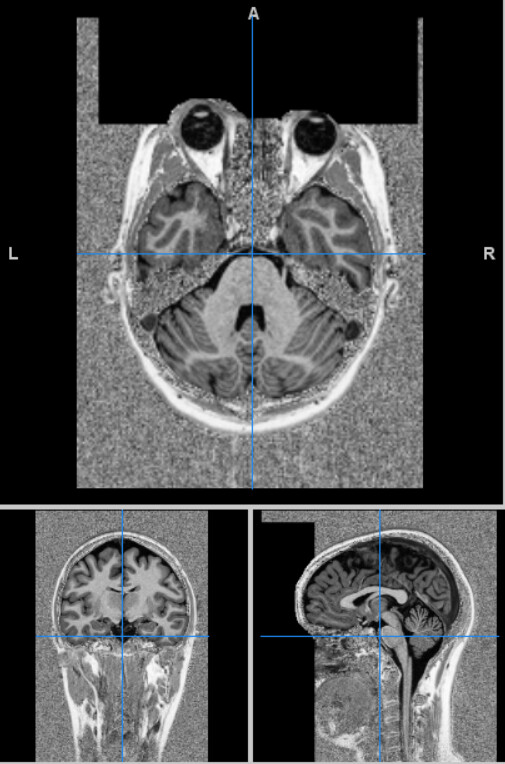

I have tried performing an initial preprocessing pipeline using fMRIPrep for data of a single subject, including structural T1- and T2-weighted volumes and rs-fMRI data. However, I get some errors.